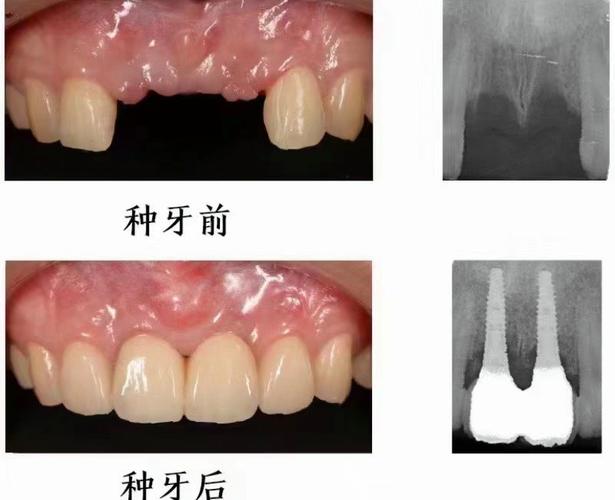

- 看案例: 要求看与你情况类似的实际案例(照片、X光片)。